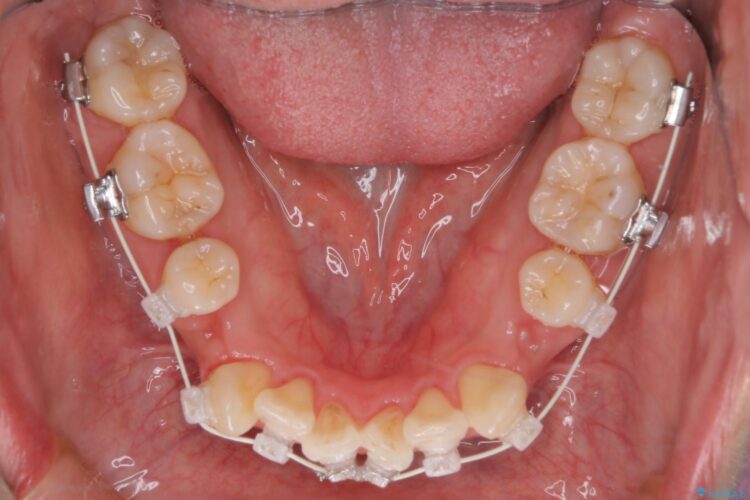

重度の叢生が認められたため、上下左右4番目の歯を抜歯しワイヤー矯正治療を行いました。

前歯のデコボコが改善され、噛みあわせも綺麗になりました。